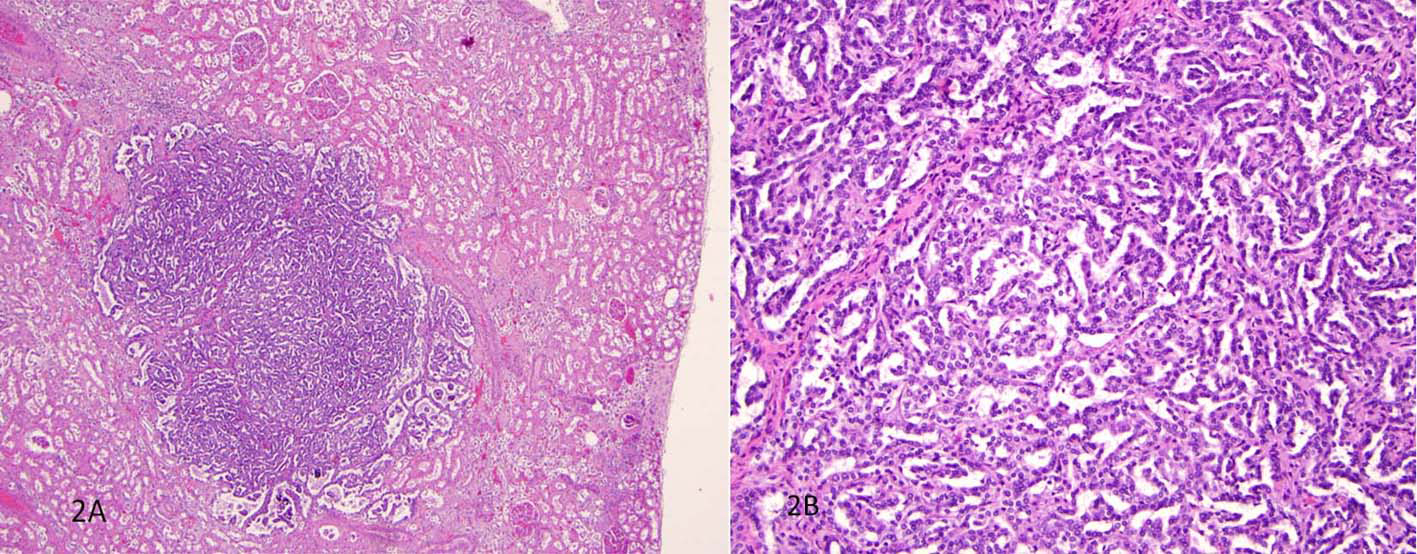

The unexpected findings were multiple well-circumscribed unencapsulated, pale yellow tumors in the subcapsular portions of both kidneys ranging from 0.2 to 0.4 cm in greatest dimension (Fig. 1). H&E sections revealed densely packed papillae or tubules lined by small, regular, cuboidal cells with rounded, uniform nuclei that lacked cytologic anaplasia and mitoses, making a diagnosis of tubulopapillary adenomas (Fig. 2).

![]() Click for large image | Figure 2. H&E sections revealed densely packed papillae or tubules lined by small, regular, cuboidal cells with rounded, uniform nuclei that lacked cytologic anaplasia and mitoses. |